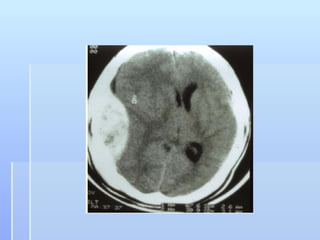

8.2. Non-contrast CT Brain                           8.2 Non-contrast CT Brain

Acute and subacute Subdural    CT Density 72.9 HU

Hematoma

8.2. Non-contrast CTBrain 8.2 Non-contrast CT Brain Acute and subacute Subdural CT Density 72.9 HU Hematoma